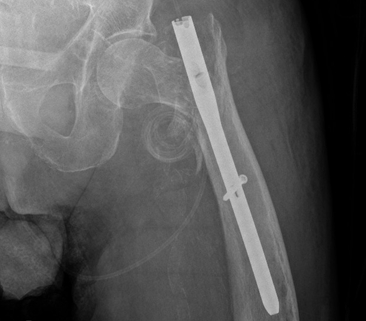

一名 85 岁男性因左股骨转子间骨折接受了短头髓钉固定术。跌倒后,检查显示头髓螺钉从内侧上移位到盆腔中。血管造影显示螺钉尖端位于髂骨分叉处 2 厘米以内,没有出血或内脏损伤的证据。

术前检查: